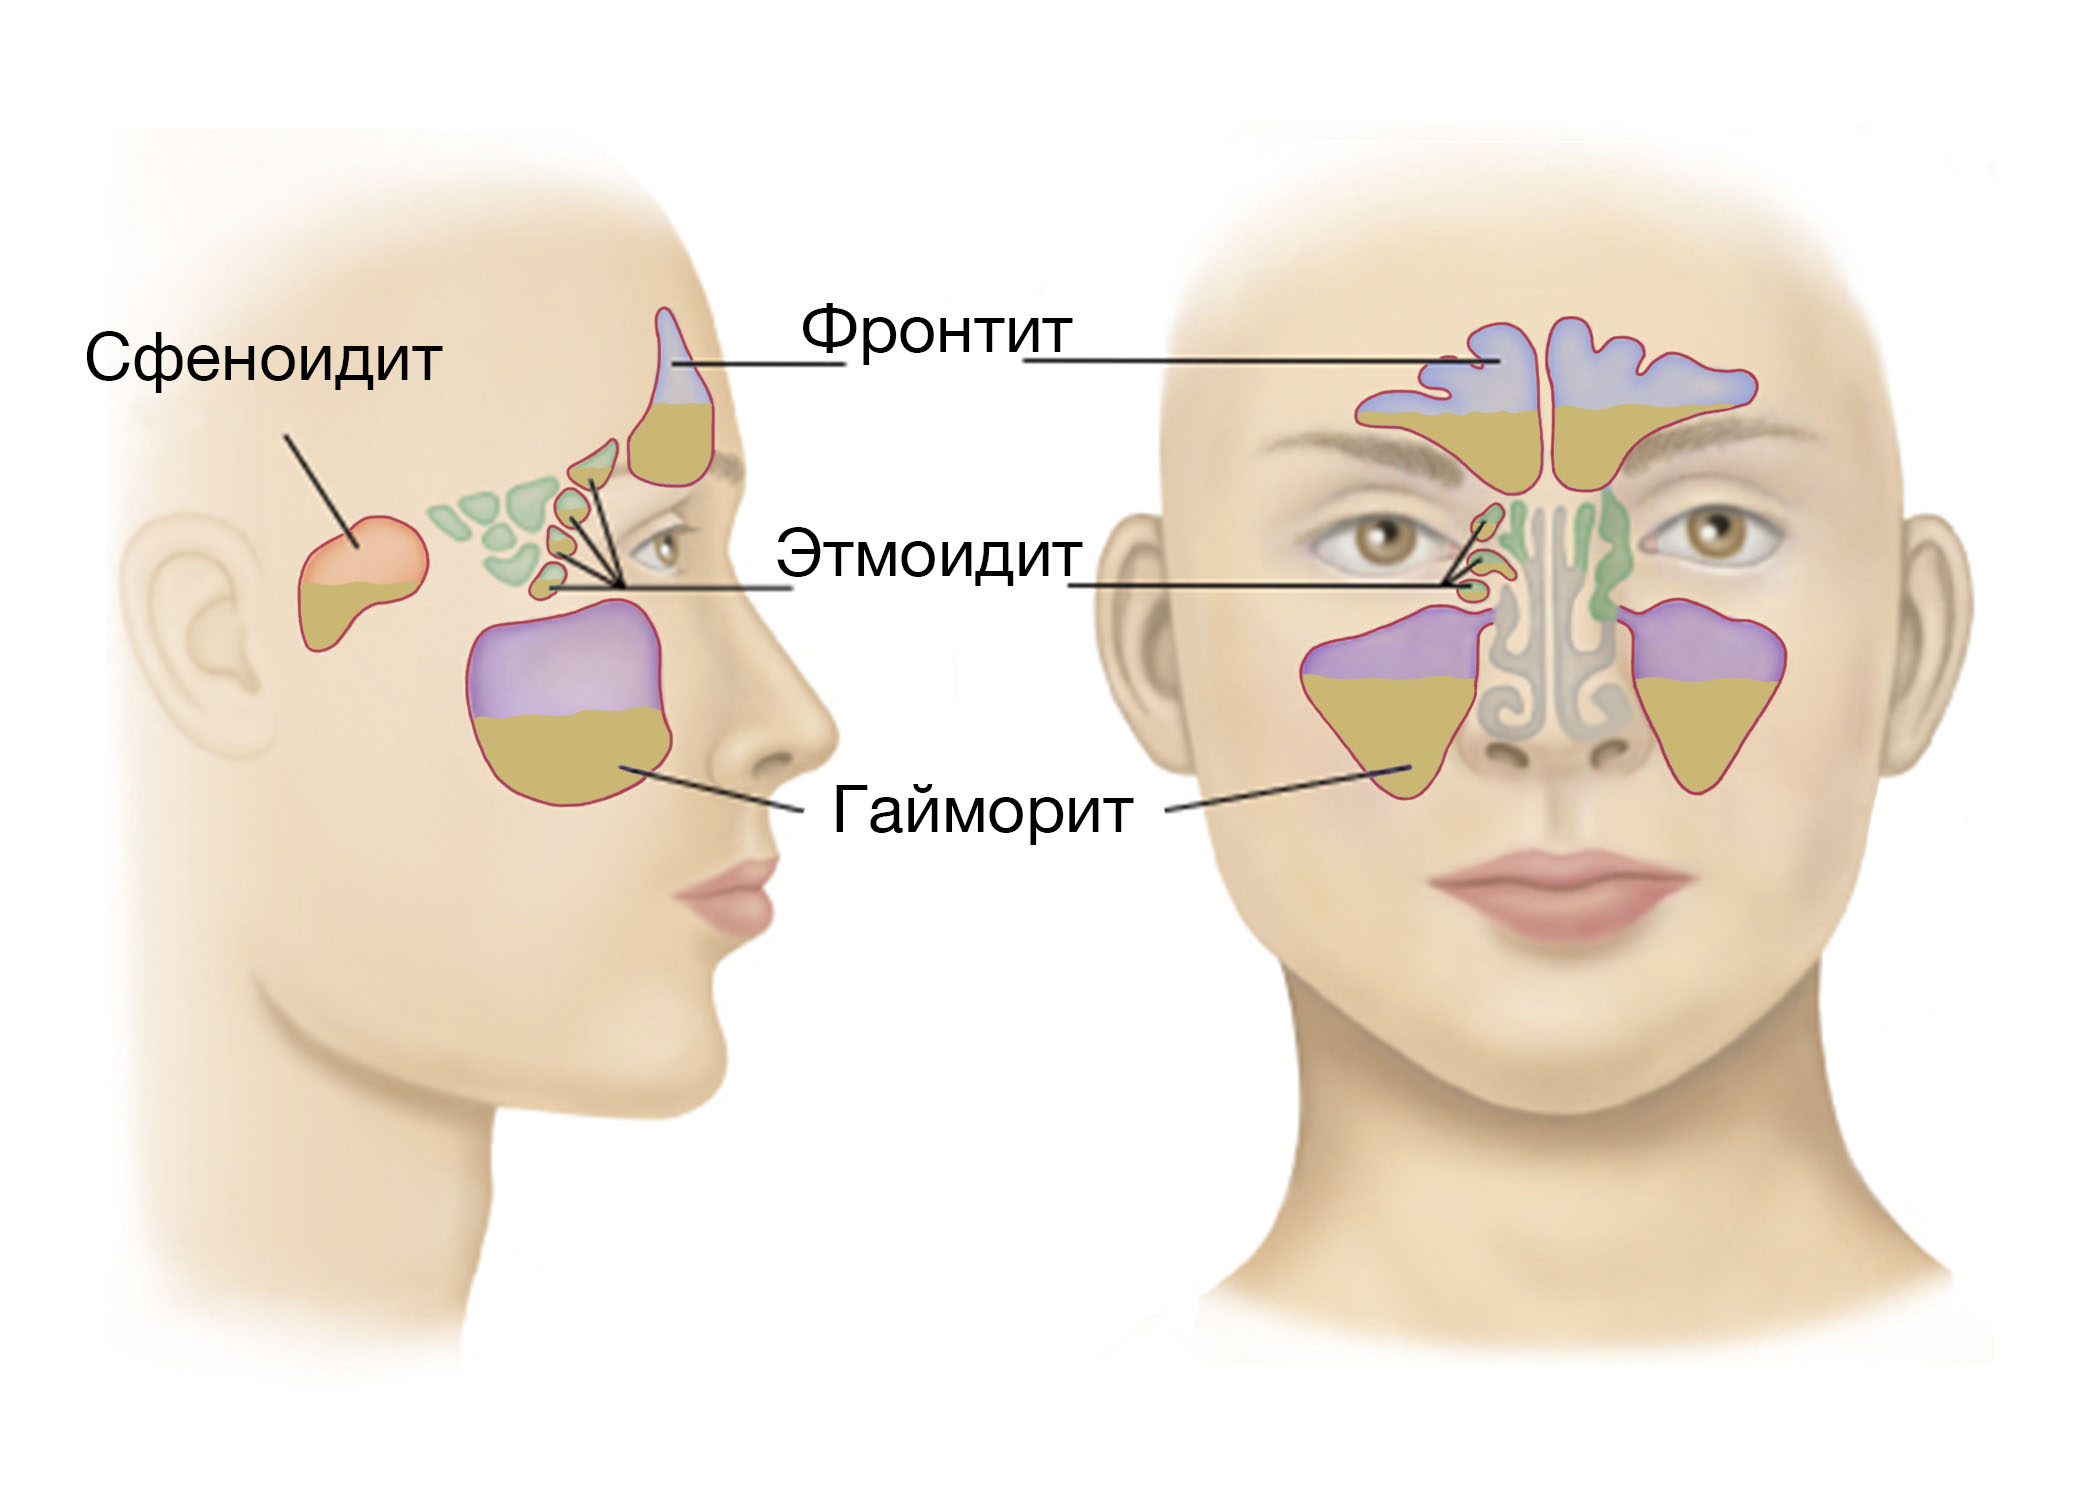

КТ-снимки хронического этмоидита: подробная визуализация